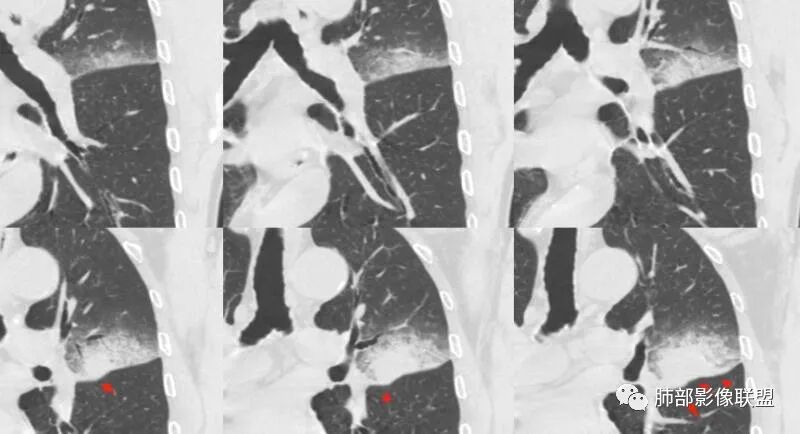

病灶沿叶间胸膜向内,支气管远端不畅,近端有扩张,所以符合外朝内病变。

外朝内无非是:占位效应,GGO边缘;支气管走形、堵塞的形态,血管,密度及强化;内部的坏死及空洞。

我标示一下,尖后段搭到一部分,前段也占了一点点。

主体在舌段

有占位效应吗?

有,斜裂局部膨隆

边缘膨隆,叶间裂有局部膨出下坠

有膨隆+收缩

密度?

实变为主,加周围模糊GGO

GGO+实变

强化如何?

强化有疑问,前面感觉有低密度的,有些图好像又均匀

不均匀中度强化

不均匀轻中度渐进强化。

整体形态

南边:

外围大,内带小

支气管?

支气管外面堵了,近端有扩张

有堵塞,有狭窄

中远端堵塞,堵塞端圆钝

炎性? 肺炎型肺癌待排

血管受侵了吧

空洞内侧软组织肿块,比较支持恶性吧

这个空洞的性质很重要,对最后诊断结果影响大,如果中间没有曲菌球,那就是偏心空洞,指向恶性,如果是曲菌球引起的新月形改变,那就不一定。至于到底是曲菌球还是偏心空洞,需要仔细看看强化情况。